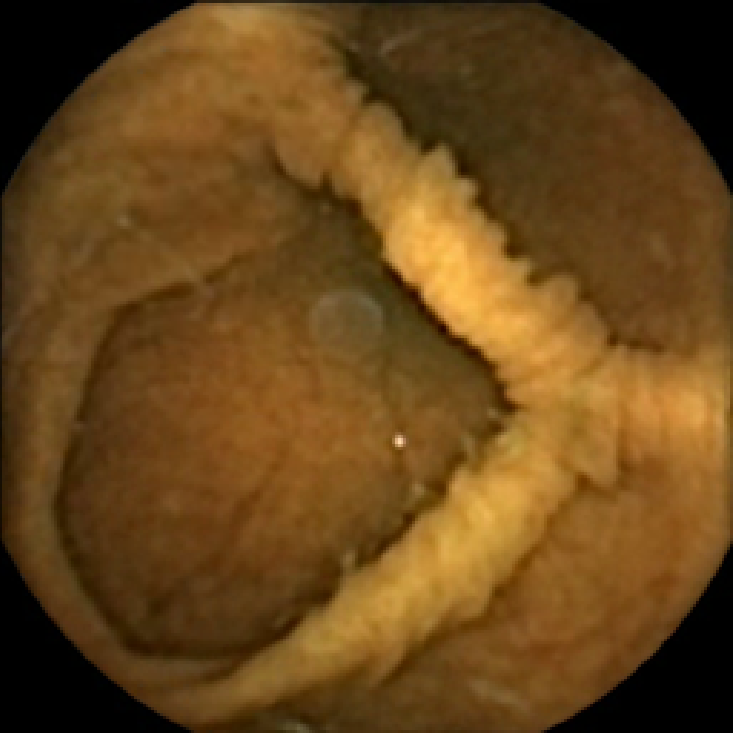

We illustrate the above considerations in Figure 4, where we compare the ellipses of inertia for a polyp frame and two frames with pronounced mucosal folds. The ellipses we plot are

| (20) |

where . The scaling term in front of is chosen so that the area of the ellipse of inertia is the same as the size of the corresponding feature.

As expected, we observe that the ellipses corresponding to mucosal folds (feature 2 in the second row and features 2 and 3 in the third row of Figure 4) are indeed much more stretched out than the ellipse corresponding to a polyp (feature 1 in the first row of Figure 4). Stretched ellipses imply higher eccentricity, thus we impose the following criterion

| (21) |

with some threshold to select moderately stretched features that are more likely to correspond to polyps.